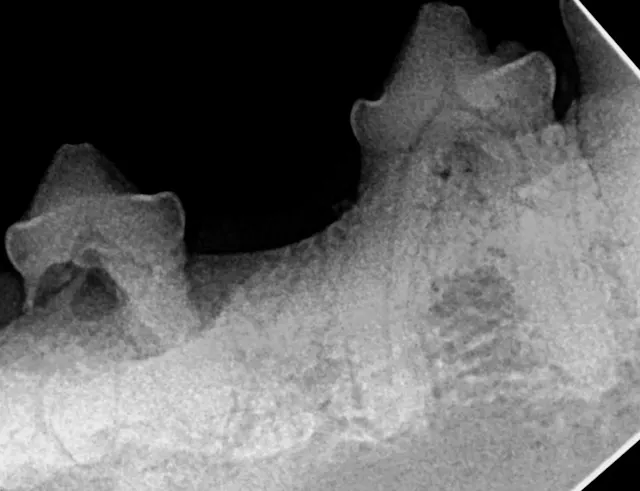

Intraoral radiograph of the left mandibular fourth premolar; the distal root is affected by external resorption that has not extended into the oral cavity.